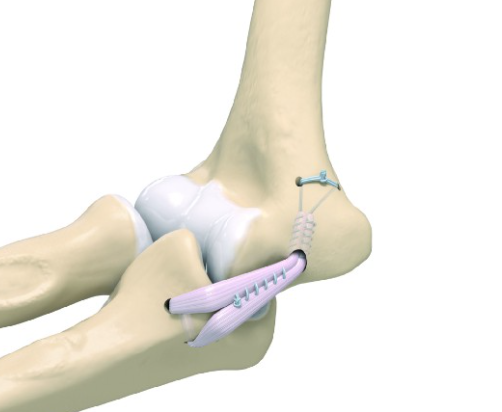

수술적 치료: 힘줄이나 인대의 파열, 성장판 손상이 심하거나 보존적 치료에 반응하지 않으면 내측측부인대 재건술, 힘줄 봉합술 등의 수술을 진행합니다. 스포츠 선수의 경우 빠른 복귀를 위해 수술적 치료가 선택될 수 있습니다